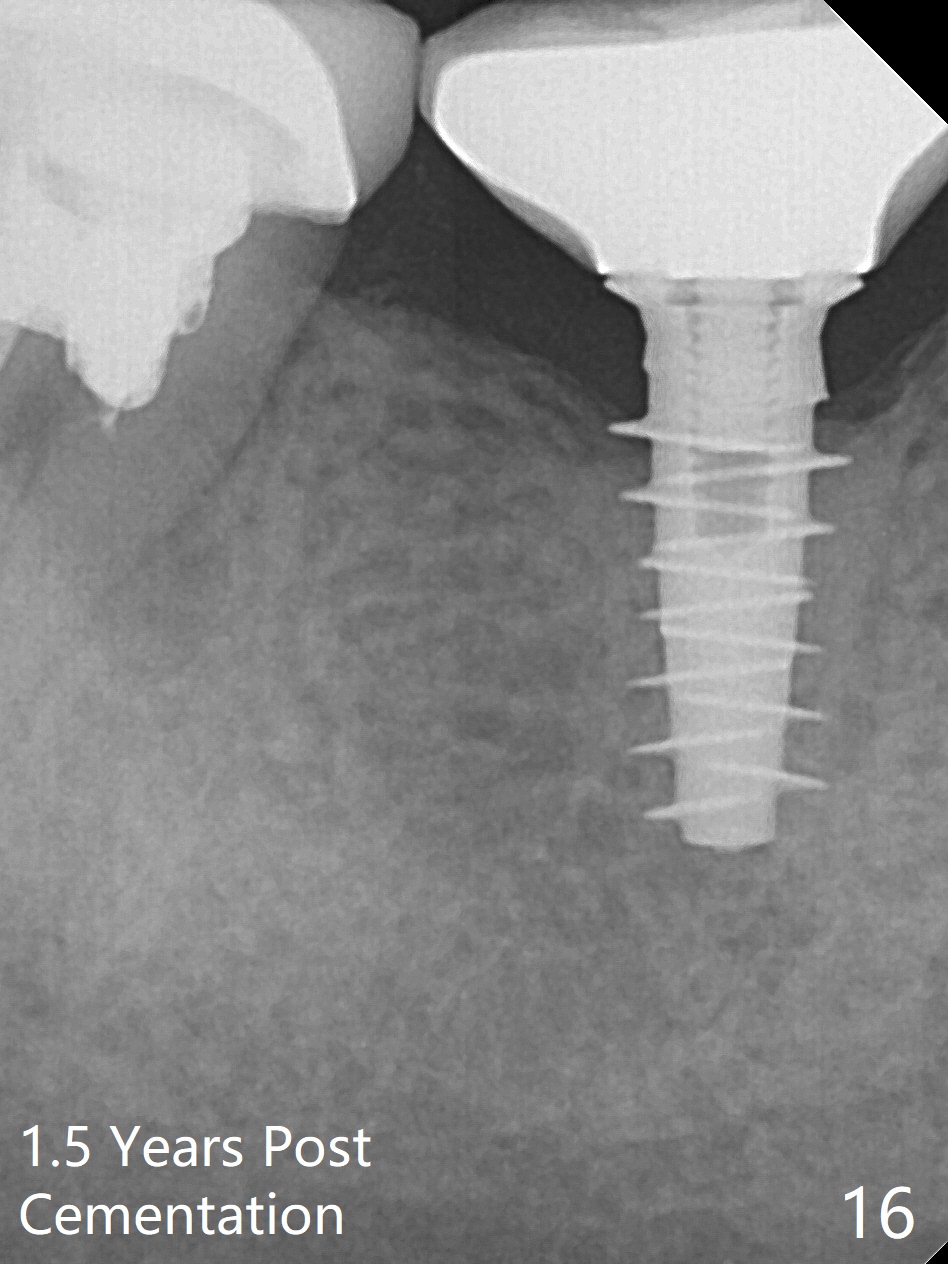

Splinted provisional is fabricated #30 and 31 one month postop. The patient returns for final restoration (single units) nearly 4 months postop (Fig.11). Since the margin is subgingival, a screw type crown is fabricated for #30 (Fig.12). The buccal gingiva looks convex after healing cap removal (Fig.13, as compared to Fig.4 (concave)). PA is taken immediately post tightening and cementation (Fig.14, 5 months postop). It appears that new bone has grown between the most coronal threads (arrows). The bone density immediately around the implant appears to increase 1.5 years post cementation (Fig.15,16). She returns because of failure of 18-20 bridge (implants will be placed at 18/19). The implant at #30 is in fact not placed deep enough; the coronal threads seem to be exposed, although there is no periimplantitis (Fig.17 CT). The tooth #31 is symptomatic; the mesial canal is missing (Fig.18 M, <). The gingiva around the crowns at #30 and 31 remains healthy 2 years 4 months post cementation (Fig.19). Metal exposure of the crown at #31 is intentional. Occlusal reduction is done to alleviate periapical re-infection (Fig.18).